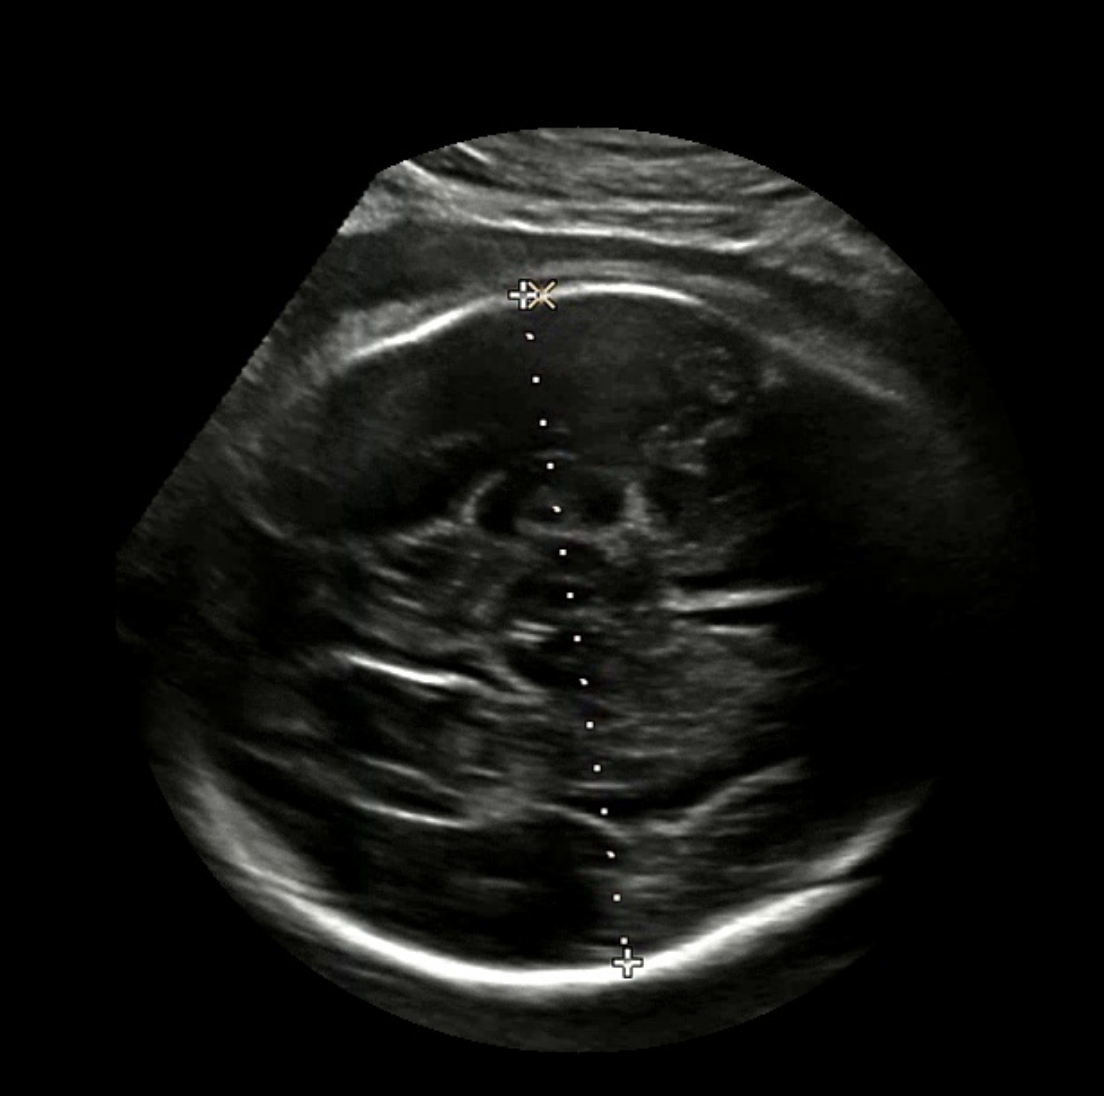

가장 큰 벽;

아직 갈 길이 멀지만 당장 큰 벽은 스케일 바 눈금을 측정하는 것이다. 즉, 배율 정보를 구하는 것이다. DICOM 파일이었다면 pixel spacing 값을 바로 사용하면 된다. 단순히 눈금 패턴을 일어보려 했는데 아래와 같이 나오는 경우도 있었다. 꽤나 힘든 과정일 것 같다. 삽질을 꽤나 해야겠다.